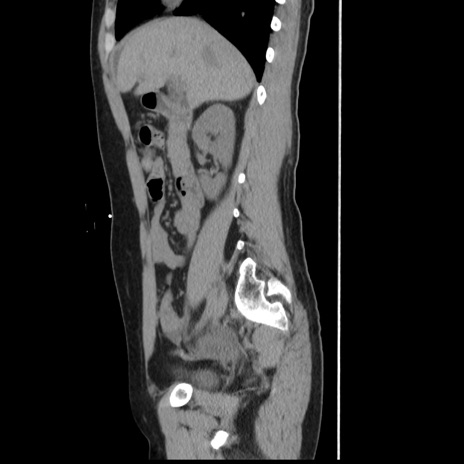

横断像

【症例】 50歳代女性

【主訴】 腹痛

【現病歴】前日生レバーを食べた。今朝に排便あり。 昼前に突然発症の腹痛を生じ、当院救急外来を受診した。

【既往歴】 子宮筋腫にてで子宮全摘後

【身体所見】 意識清明、腹部:平坦、軟、下腹部やや左を中心に圧痛・反跳痛あり、筋性防御あり

【データ】WBC 7800、CRP 0.07